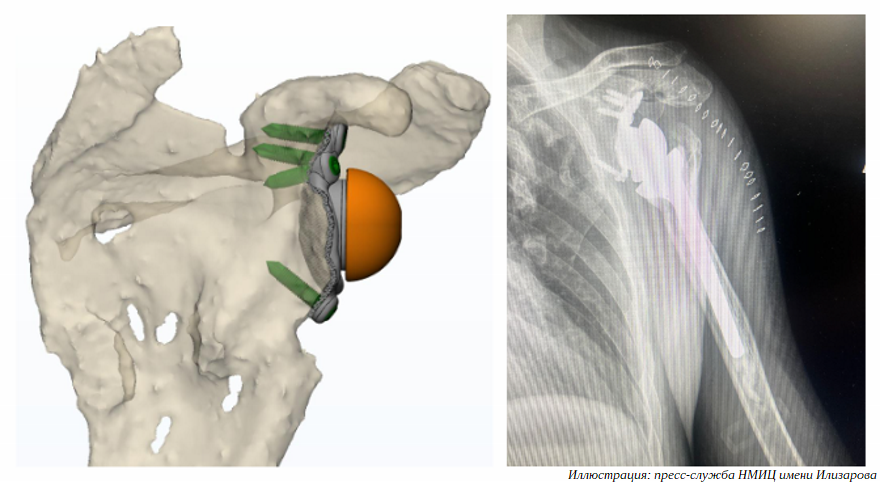

Титановый имплантат изготовлен по антропометрическим данным пациента. Как только индивидуальный протез суставного отростка лопатки был доставлен в Курган, хирурги отделения №8 Национального медицинского исследовательского центра травматологии и ортопедии имени академика Г. А. Илизарова провели сложную операцию по установке персонифицированной конструкции.

Пациент обратился в центр с жалобами на боли в плечевом суставе и ограничение движений, сообщает пресс-служба НМИЦ имени Илизарова. Мужчина не мог пользоваться рукой в быту и профессиональной деятельности из-за ранее полученной боевой травмы. Обследование показало, что в результате травмы возникла не только деформация проксимального отдела плеча, но и сформировался тотальный дефект суставного отростка лопаточной кости. Этот отросток попросту отсутствовал.

«В такой ситуации невозможно надежно фиксировать лопаточный компонент. Даже если бы это получилось, биомеханика эндопротеза плечевого сустава была бы крайне нарушена. Поэтому совместно с московскими инженерами нами был разработан индивидуальный лопаточный компонент реверсивного эндопротеза с помощью аддитивных технологий», — рассказал руководитель Клиники реконструктивно-восстановительной хирургии крупных суставов НМИЦ имени Илизарова Николай Чирков.

В ходе операции врачи столкнулись с рядом серьезных трудностей: вся полость плечевого сустава и окружающие участки были заполнены плотной рубцовой тканью, поэтому перед установкой протеза хирургам предстояло ликвидировать фиброзно-спаечный процесс, что и было успешно выполнено. Хирурги зафиксировали лопаточный компонент, компенсировали все костные дефекты и установили реверсивный протез плечевого сустава. Мышцы пациента приведены в тонус, плечевой сустав стал мобильным, мужчина вновь может полноценно пользоваться рукой.